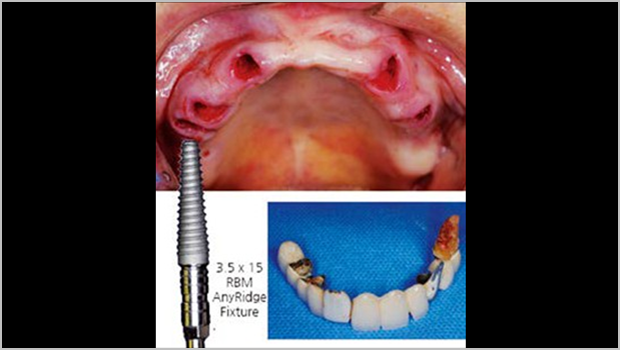

Clinical case: Extraction of all teeth in upper maxilla,

immediate implant placement, & provisionalization

- Courtesy of Dr. Iulian Filipov, Romania -

Keywords

AnyRidge, immediate placement, immediate provisionalization, maxillary fully edentulous case, initial stability, edentulous, Dr. Iulian Filipov, R2GATE, MEGA ISQ

Products:

AnyRidge implant system, Mega ISQ, R2GATE